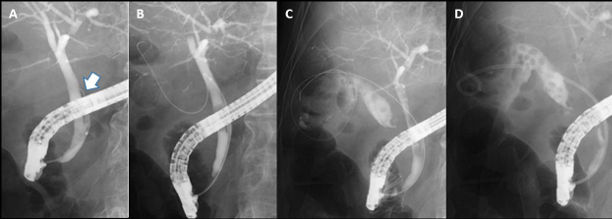

図2 内視鏡的胆嚢ドレナージ

A; 胆嚢と総胆管をつなぐ胆嚢管(矢印)にガイドワイヤーが挿入されている。

B; ガイドワイヤーが引き続き胆嚢内まで挿入された。

C; 造影で胆嚢結石を疑う陰影欠損が多発していることが確認された。ガイドワイヤーは胆嚢内に十分に留置された。

D; 内視鏡的に胆嚢内にドレナージチューブが挿入された。